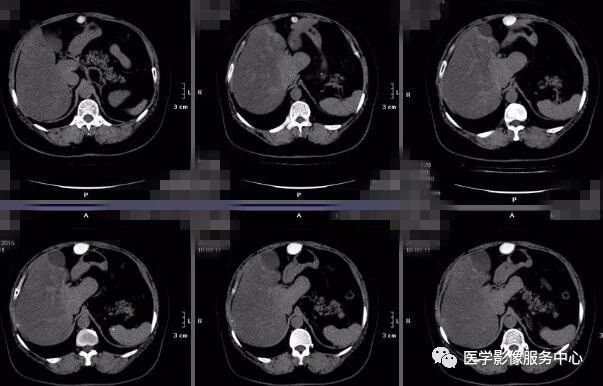

放射線技師向け kenminkei11. 2.MRIのパルスシーケンス 表在性軟部腫瘍では病変部位や形態が様々で あり,プロトコールを標準化しづらい.当院で 表在性軟部腫瘍の画像診断 391 図1石灰化上皮腫 (a)(b)(c)後背部正中の皮下腫瘤は,MRIのT1強調像,T2強調像でともに低信号で辺縁に. 肝細胞癌はt2強調画像、拡散強調画像で高信号、t 1 強調画像では低信号を呈している。造影ダイナミック検査早期相ではgd.

Nuclear Magnetic Resonance (Image). リウマチは関節内に存在する滑膜という組織が異常増殖し、関節内に慢性の炎症を生じる病気で、進行するとさまざまな機能障害を引き起こします 現在、当クリニックでは上腹部MRI検査として、横断像を4シーケンス<T1(in、 out Phase)T2 HeavyT2 DWI>、冠状断. T1強調像(Axial) T2強調像(Axial) 内膜症性嚢胞(チョコレート嚢胞) multiplicity.

MRI ・T2強調像でのjunctional zone. 15分で分かる(?)MRI 古典力学的説明※1 MRI原理へのいざないPart 1 1個のプロトンから15分単位で理解できる(?) 基本的な信号強度 Part 1 プロトン密度、T1、T2と信号強度 ※学部学生は最低でもPart 1を理解すること. 4.mri:撮像法と画像所見 角谷 眞澄 藤永 康成 はじめに 肝疾患の診断にmriが期待されるのは,その優れた 組織コントラスト能によるところが大きい.t1強調像, t2強調像にて肝細胞性結節性病変は様々な信号強度を.

肝胆系统和胰腺的mri和ct 肝脏

影像学解析 肝脏良性肿瘤案例 丁香园

肝脏占位 医联

病例 奇特的肝占位性病变